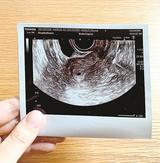

元記者の 不妊治療、しています。(17) 妊娠5週目 4ミリの胎嚢

山陰

2022/12/2 04:00